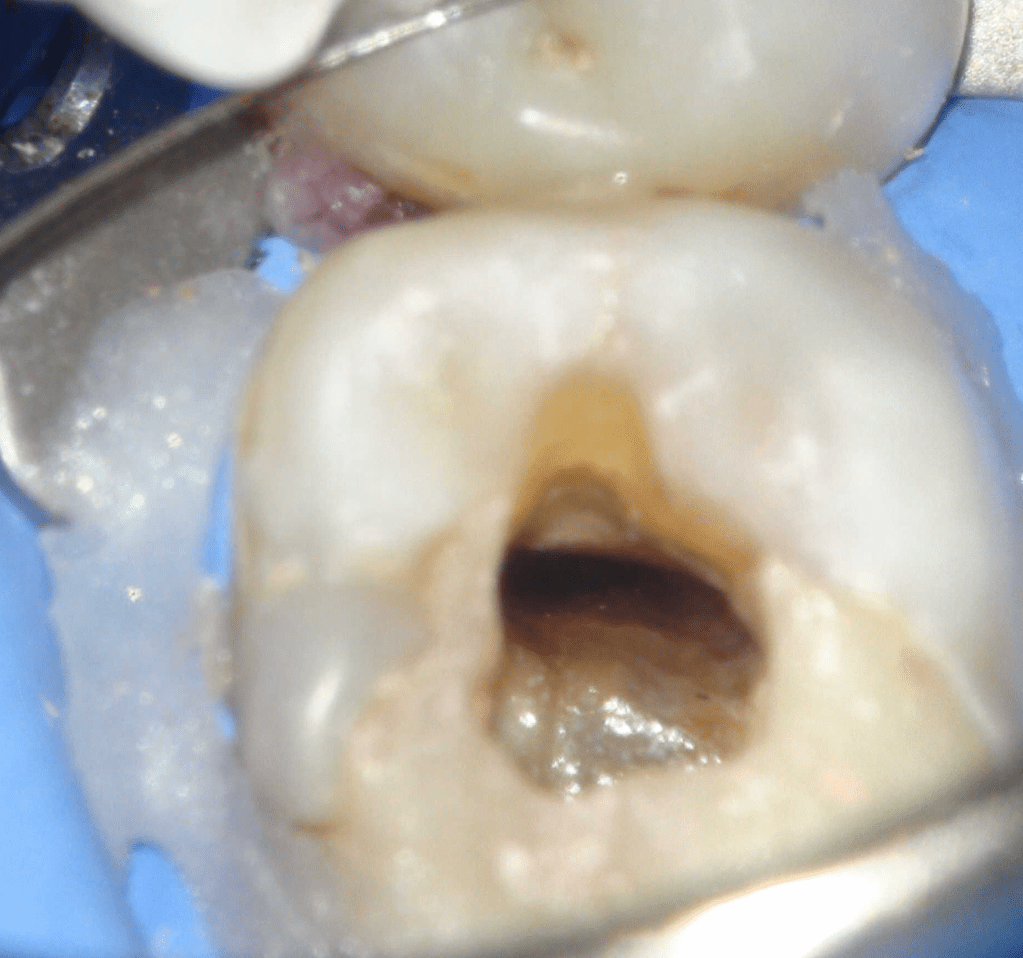

Reco pre-endo, molar inferior